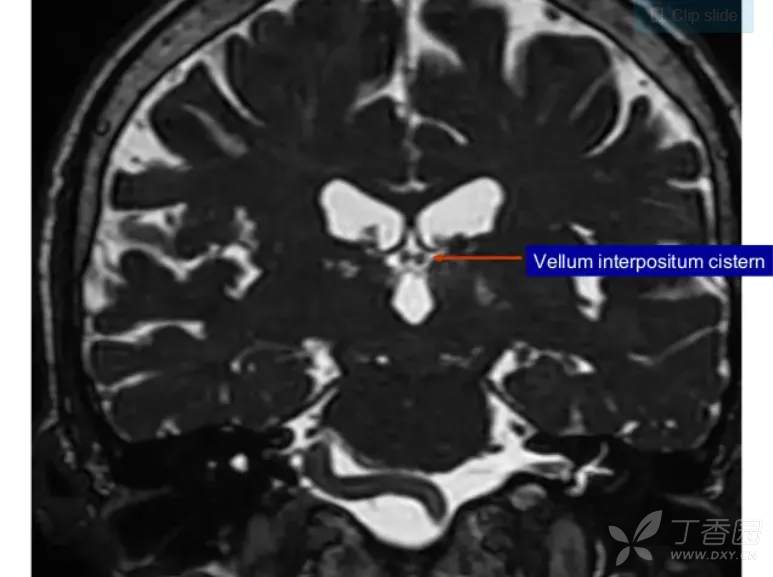

帆间池

帆间池 cistern of velum interpositum, 又称中间帆腔或第三脑室上池,位于第三脑室顶的上方、穹隆体和穹隆连合的下方。

冠状位示意图- CVI:前髓帆间隙,CC:胼胝体,ICV:大脑内静脉,F:穹窿,VL:侧脑室,T:丘脑,CN:尾状核,3V:第三脑室,CP:脉络丛。

它是一尖向前的三角区,两前外侧界为穹隆的内侧缘,后界为胼胝体压部。

此腔可经胼胝体压部的下方通大脑大静脉池。

在临床工作中,应注意帆间池与第三脑室顶部的区别:

1、帆间池的层面较高,第三脑室顶部层面较低;

2、帆间池后界是胼胝体压部,第三脑室顶部的后界为松果体;

3、帆间池为尖向前的三角区,不与侧脑室前角相连;而第三脑室前部为矢状位的狭长裂隙,前端可达侧脑室前角。